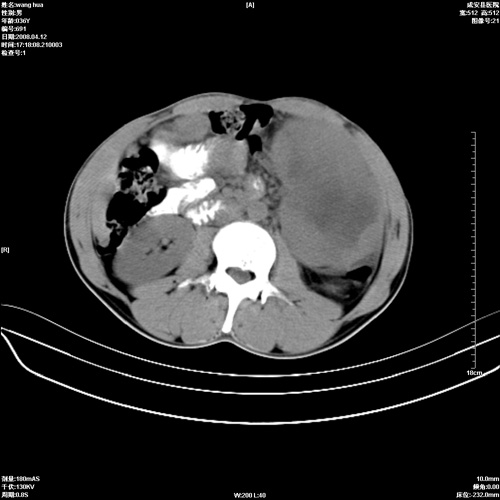

标题: CT12809:男36岁,自感上腹胀5天,B超诊断为脾肾之间占位,血 [打印本页]

标题: CT12809:男36岁,自感上腹胀5天,B超诊断为脾肾之间占位,血

请各位老师先分析一下定位 明天做增强

确实需要强化!先大胆预测一下,来源于脾脏的占位,血管瘤或淋巴瘤可能性大。

脾脏肿瘤,有钙化,增强再说

脾脏病变,密度不均,可见钙化,考虑脾血管瘤,建议增强

脾脏明显增大,其内见巨大低密度灶,境界不清,病史较短,考虑恶性病变脾血管内皮细胞肉瘤可能。建议增强扫描与脾脏淋巴瘤及血管瘤鉴别。